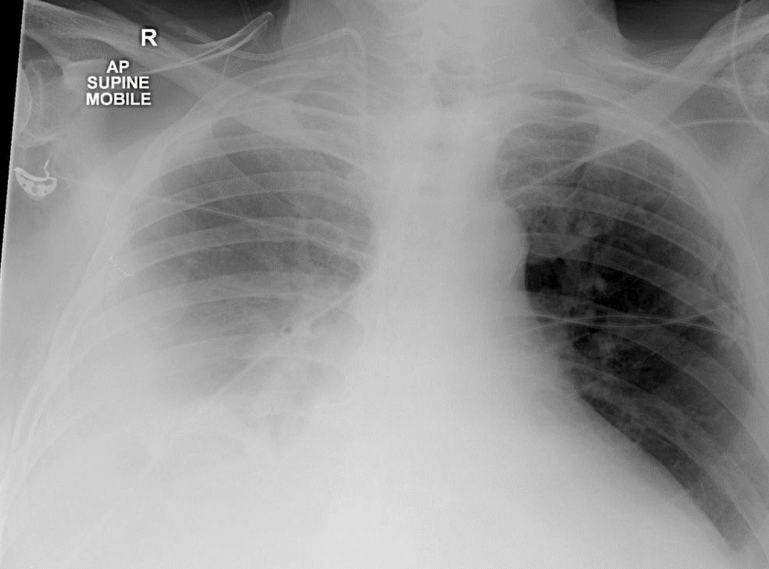

right side peunothorax

tracheal deviation to left

compresed/shifted heart

absent vasculature on right